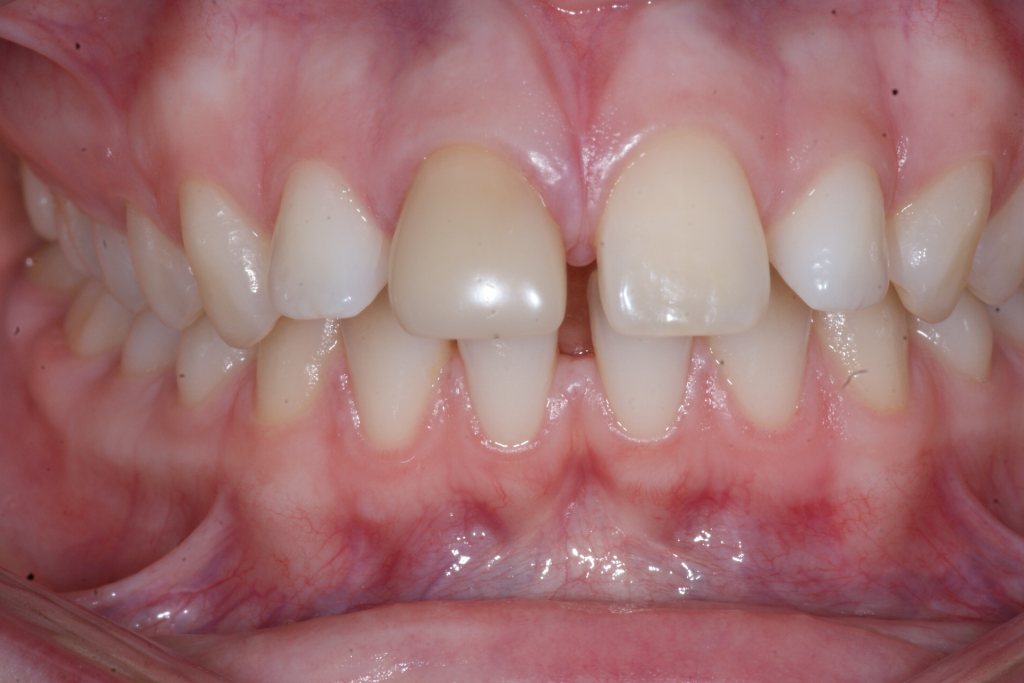

Correction d’une malocclusion de type Classe II division 1 avec excès d’espace aux 2 arcades.  Des appareils fixes (boîtiers) et une expansion palatine furent nécessaires pour améliorer ce sourire.  Traitement chez une adolescente, réalisé en 26 mois.